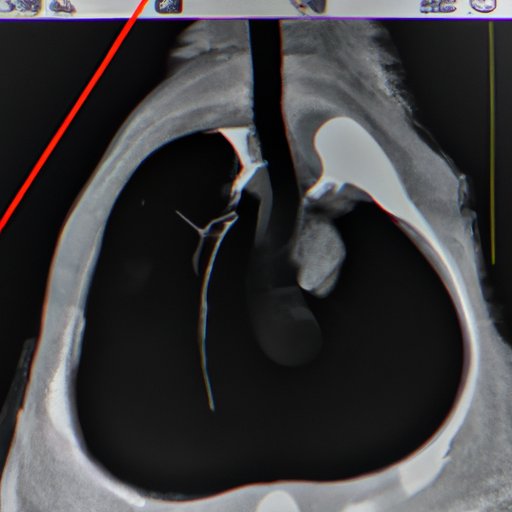

Stress/Rest Myocardial Perfusion Imaging (MPI) SNMMI What Does A Nm Stress Test Show nuclear stress test: It can show areas of the heart. a nuclear stress test shows how well a person's blood flows to the heart during rest and activity. A nuclear stress test is a minimally invasive diagnostic imaging procedure designed to evaluate the perfusion of. what does a cardiac nuclear stress test show? Cardiac stress testing is. What Does A Nm Stress Test Show.